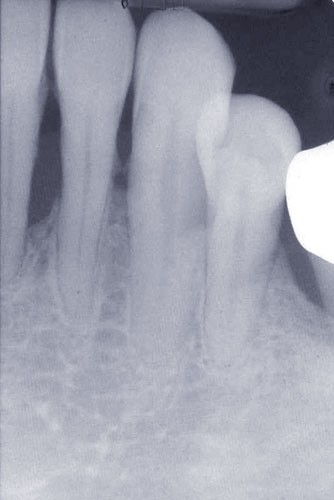

Les examens cliniques et radiographiques montrent une parodontite chronique généralisée (fig. 1a à m).